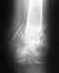

Травма голепностопа

Здравствуйте!В 2000 после ДТП пострадал левый голеностопный сустав.Нога была вывернута назад.Полный разрыв ахилла.Был установлен сапожок и наложены швы на ахилл.Сейчас ставят диагноз деформирующий остеартроз.Нога ещё больше выворачивается кнаружи.Обьём движения ограничен.Каждый день боли в суставе.Предлагают артродез,но у меня колебания по этому поводу,в голове одна мысль что буду заметно хромать.Хотя и сейчас не всегда ровно хожу.Прошу помочь и поддержать советом.спасибо